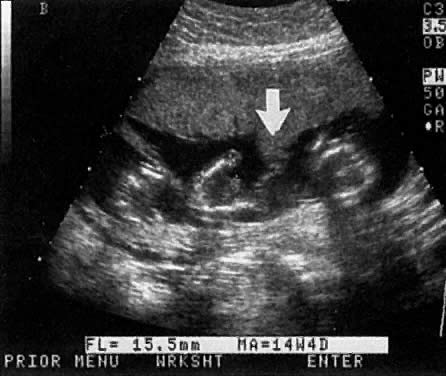

DATING

Crown-rump measurements at 6 to 10 weeks are accurate in assigning gestational age (95% confidence interval [CI] ± 3 to 5 days). This compares to BPD assessment at 16 to 24 weeks, which has a 95% CI accuracy of plus or minus 7 to 10 days. In contrast, as noted by Gardosi,16 LMP dating is less accurate, with a 95% CI of -9 to +27 days. The inaccuracy of LMP dating can lead to errors in assessing both preterm and post-term pregnancy rates, as well as false-positive PANAFP screens. A recent, well-referenced editorial by Gardosi16 discusses the inaccuracy of LMP dating and advocates routine ultrasound confirmation of dates.

Robinson and Fleming17 published the first crown-rump length tables. More recent studies with timed ovulation have shown that their table underestimated gestational age by about 1 week (Table 3).18,19 A simple rule at early gestation is that a 7-mm embryo is about 7 menstrual weeks and grows about 1 mm/day for the next 3 weeks. Crown rump lengths at gestational ages greater than 10 weeks are less accurate.